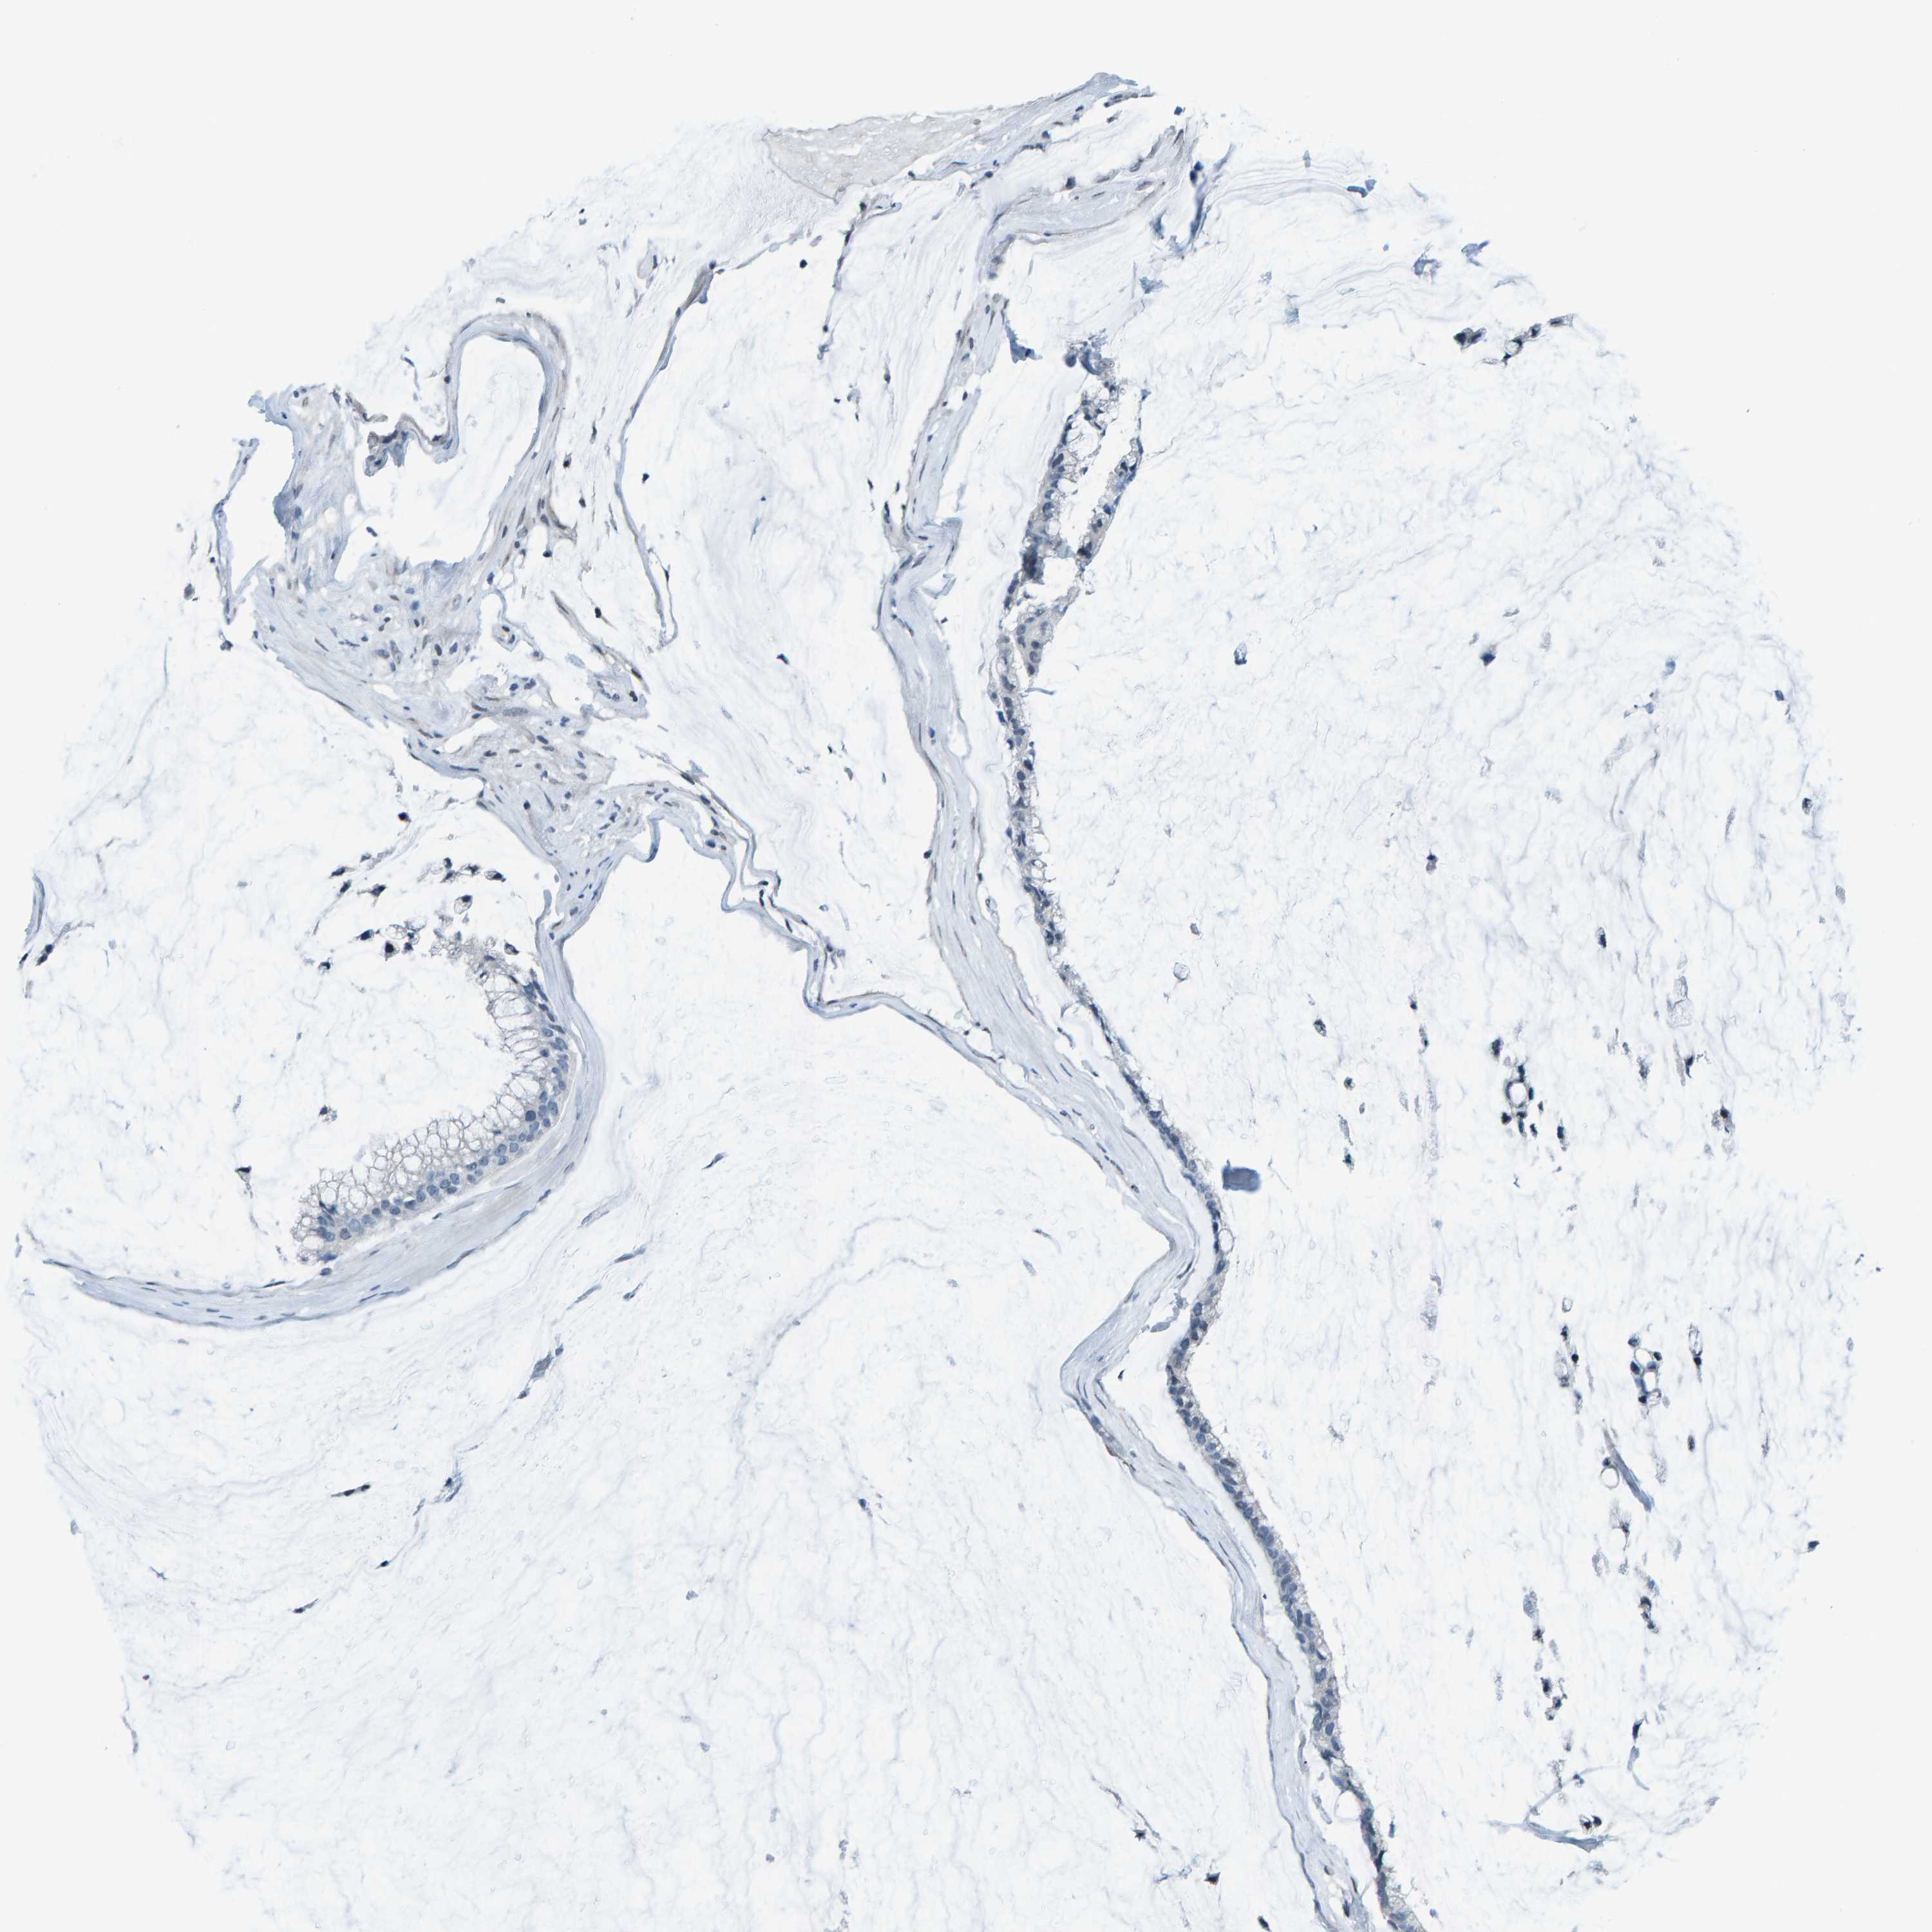

OVARIAN CANCER - Protein expressioni

A mouse-over function shows sample information and annotation data. Click on an image to view it in a full screen mode. Samples can be filtered based on level of antibody staining by selecting one or several of the following categories: high, medium, low and not detected. The assay and annotation is described here.

Note that samples used for immunohistochemistry by the Human Protein Atlas do not correspond to samples in the TCGA dataset.

Antibody stainingi

Antibody staining in the annotated cell types in the current human tissue is reported as not detected, low, medium, or high, based on conventional immunohistochemistry profiling in selected tissues. This score is based on the combination of the staining intensity and fraction of stained cells.

Each image is clickable and will lead to virtual microscopy that enables deeper exploration of all samples and also displays staining intensity scores, fraction scores and subcellular localization as well as patient and tissue information for each sample.

CAB002672

Cystadenocarcinoma, serous, NOS